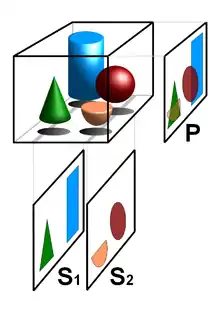

Volume rendering is a set of techniques used to display a 2D projection of a 3D discretely sampled data set, typically a 3D scalar field. A typical 3D data set is a group of 2D slice images acquired, for example, by a CT, MRI, or MicroCT scanner. These are usually acquired in a regular pattern (e.g., one slice every millimeter) and usually have a regular number of image pixels in a regular pattern. This is an example of a regular volumetric grid, with each volume element, or voxel represented by a single value that is obtained by sampling the immediate area surrounding the voxel.

To render a 2D projection of the 3D data set, one first needs to define a camera in space relative to the volume. Also, one needs to define the opacity and color of every voxel. This is usually defined using an RGBA (for red, green, blue, alpha) transfer function that defines the RGBA value for every possible voxel value.

For example, a volume may be viewed by extracting isosurfaces (surfaces of equal values) from the volume and rendering them as polygonal meshes or by rendering the volume directly as a block of data. The marching cubes algorithm is a common technique for extracting an isosurface from volume data. Direct volume rendering is a computationally intensive task that may be performed in several ways.